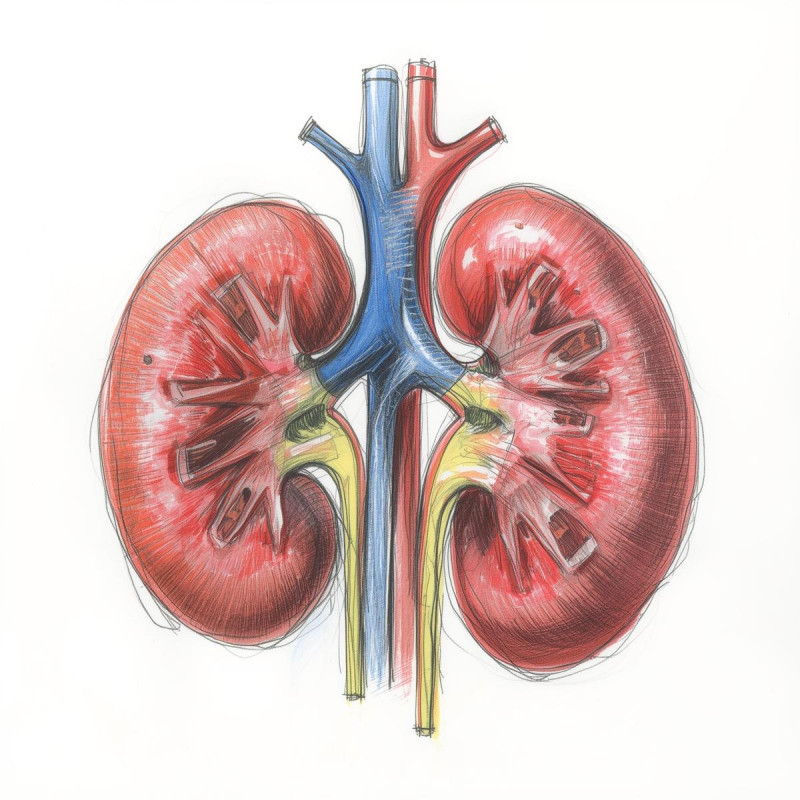

Przewlekła choroba nerek (PChN) dotyka blisko 10% populacji dorosłych na całym świecie. Szacuje się, że w Polsce problem ten może dotyczyć nawet 4 milionów osób, z czego ogromna większość nie jest świadoma swojej choroby. Nerki pełnią funkcję filtracyjną, usuwając toksyny i nadmiar wody z organizmu, a także regulują ciśnienie tętnicze i produkcję czerwonych krwinek. Ich niewydolność wpływa destrukcyjnie na cały organizm, zwiększając ryzyko chorób układu krążenia, w tym zawałów serca i udarów mózgu.

Choroby nerek są nazywane „cichymi zabójcami”, ponieważ w początkowych stadiach przebiegają niemal bezobjawowo. Kiedy pojawiają się wyraźne dolegliwości, takie jak przewlekłe zmęczenie, obrzęki kończyn czy zmiany w oddawaniu moczu, funkcja nerek jest często już poważnie upośledzona.